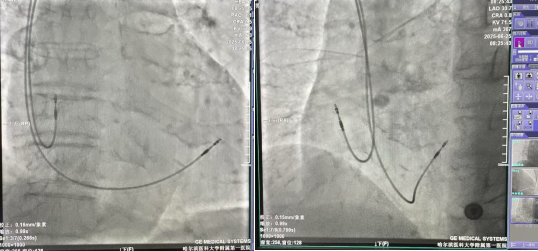

近日,哈医大一院群力院区老年病科成功为一名100岁高龄的赵大爷(化名)实施了心脏起搏器植入手术。面对老人复杂的病情,心房纤颤伴慢心室率及间歇三度房室传导阻滞,团队凭借精准医疗技术挑战超高龄危重心脏病治疗极限。术后老人恢复顺利,生活质量显著提升。

手术过程中,团队精准操作,巧妙应用微量镇静药物,确保了流程高效顺畅。整个手术仅用时约1小时,成功为赵大爷植入了心脏起搏器,解决了困扰老人的致命性心动过缓问题。